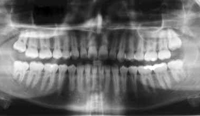

Panorex X-Rays

A panorex x-ray provides a full view of the upper and lower jaws, teeth, temporomandibular joints, and sinuses. It clearly shows impacted teeth or other intrabony abnormalities, and surrounding anatomy.

Panorex x-rays are often used to examine for wisdom teeth. This type of x-ray can show the relationship of the developing tooth roots to the mandibular nerve and maxillary sinus cavities. Usually, a panorex needs to be taken within the last year to accurately show the level of development of the tooth roots.